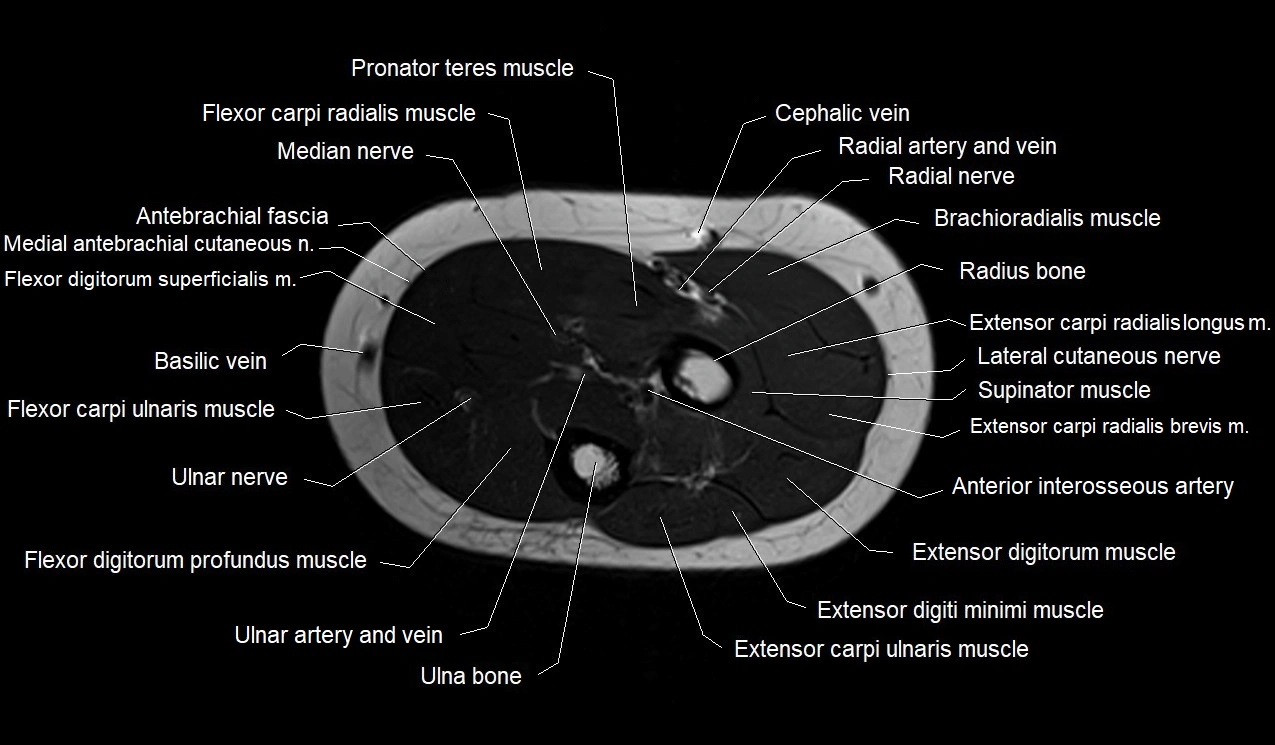

MRI images

image